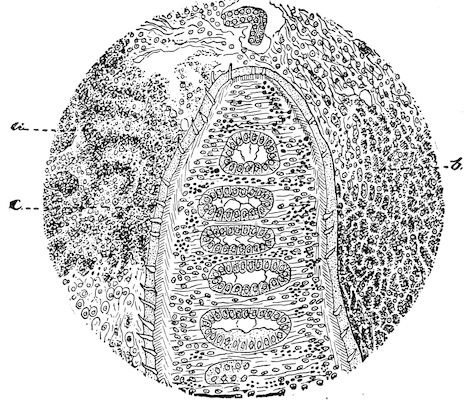

Lesions. The lesions are represented by abnormal and irregular thickening around the interarticular cartilages. The cartilage is thickened, compressible, very spongy and without regular ossification. Diffused periostitis exists principally towards the extremities of the bone. Beneath the periosteum the surface of the bone appears rough and softened. On section the medullary canals are seen to be enlarged and filled with marrow of a gelatinous character. The Haversian canals are dilated, and the entire tissue appears very vascular. Chemical analysis proves that the mineral constituents of the bone, particularly the phosphates, have diminished by one-half; the organic constituents on the other hand are increased in a similar ratio, but the ossein is abnormal. Ossification has, in a word, been incomplete.

Fig. 8.—Transverse section through the middle region of the face in a pig suffering from osseous cachexia.

18In the final stages, the bones may be cut with a knife, and a time arrives when bony tissue seems completely to have disappeared; thus, as shown in Fig. 8 herewith, it was possible to cut the entire head of a pig into thin slices without the slightest difficulty. All parts of the head had been affected by the softening change.